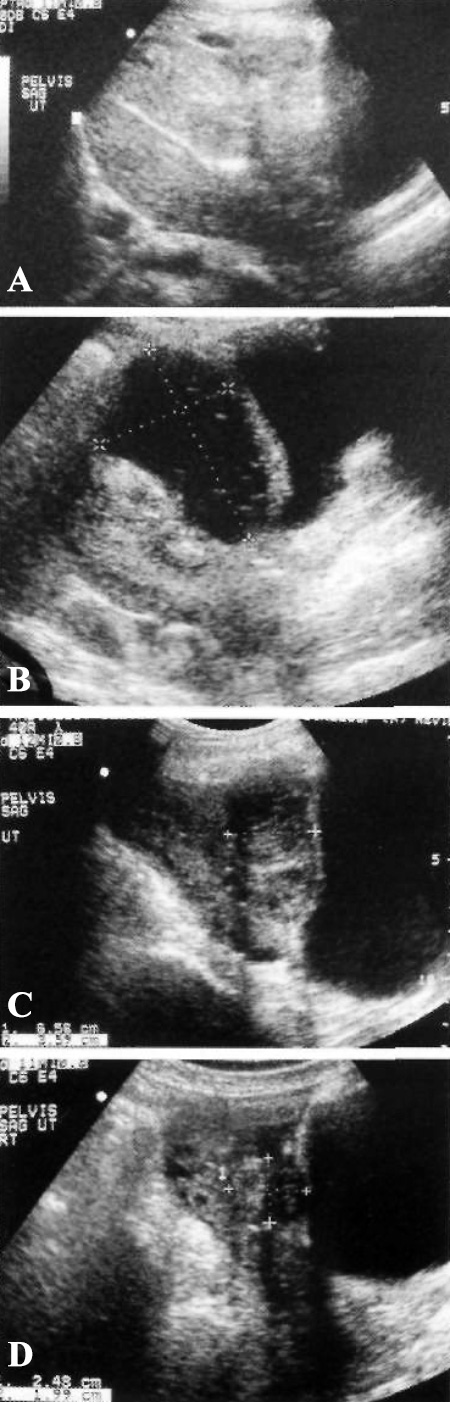

Фото 3. Гематома пузырного лоскута. А – УЗИ в сагиттальной плоскости: определяется гетерогенное скопление между нижним сегментом матки и мочевым пузырем на 3-й день после кесарева сечения. В – УЗИ этой же пациентки через 5 недель: отмечается разрешение гематомы. С – через 3 месяца. D – через 6 месяцев

Кесарево сечение подразумевает рассечение тканей с целью доступа в экстраперитонеальное пространство между передней частью нижнего сегмента матки и задней частью мочевого пузыря, таким образом обеспечивая доступ для проведения нижнего поперечного разреза стенки матки. Именно в этой области часто образуются гематомы разного размера – так называемые «гематомы пузырного лоскута», – которые на УЗИ и КТ визуализируются как гетерогенные скопления (фото 3). Нужно отметить, что в таких случаях гематома может распространяться под серозным покровом вокруг матки, вдоль широкой связки и проникать в забрюшинное пространство.

УЗИ: Гематома пузырного лоскута